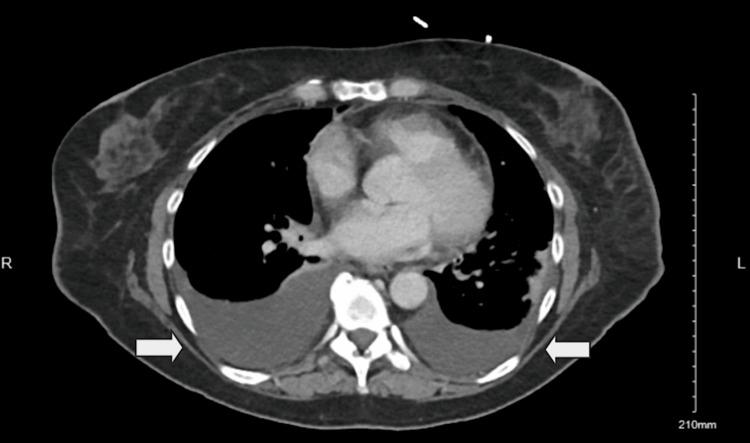

Imatinib, a tyrosine kinase inhibitor, is widely used for treating gastrointestinal stromal tumors (GISTs) and chronic myeloid leukemia (CML). While commonly associated with mild fluid retention, significant pleural effusion is an uncommon but potentially serious adverse effect. We present a case of recurrent pleural effusions secondary to imatinib therapy in a 62-year-old female patient with metastatic lung adenocarcinoma and a concurrent GIST harboring an exon 9 mutation. She was initiated on imatinib 400 mg daily, later increased to twice daily. Within weeks, she developed progressive dyspnea, and imaging revealed large bilateral pleural effusions. Pleural fluid analysis demonstrated an exudative effusion, with cytology and microbiological studies ruling out infection or malignancy. Cardiac function was preserved, and there were no signs of volume overload. She underwent multiple thoracenteses for symptomatic relief. Due to recurrent pleural effusions, imatinib was permanently discontinued, leading to complete resolution of the effusions. Subsequent treatment with sunitinib was not tolerated due to severe mucositis and cytopenias. Despite discontinuation of targeted therapy, both her GIST and metastatic lung cancer remained stable under surveillance. While pleural effusions are frequently reported with dasatinib, they are rare with imatinib. The proposed mechanisms include inhibition of platelet-derived growth factor receptors (PDGFRs), leading to increased vascular permeability, impaired lymphatic drainage, and renal sodium retention. Dose reduction may mitigate fluid retention; however, our patient developed significant pleural effusions at standard dosing, necessitating treatment discontinuation. This case underscores the importance of recognizing pleural effusion as a rare but serious adverse effect of imatinib therapy. Clinicians should maintain a high index of suspicion for drug-induced pleural effusions, particularly in the absence of other etiologies, and consider discontinuation if clinically indicated. Early recognition and management can prevent complications and improve patient outcomes.

伊马替尼是一种酪氨酸激酶抑制剂,广泛用于治疗胃肠道间质瘤(GIST)和慢性粒细胞白血病(CML)。虽然通常与轻度液体潴留有关,但大量胸腔积液是一种罕见但可能严重的不良反应。我们报告一例62岁女性患者,患有转移性肺腺癌和同时存在外显子9突变的GIST,因伊马替尼治疗继发反复胸腔积液。她开始每天服用400毫克伊马替尼,后来增加到每天两次。几周内,她出现进行性呼吸困难,影像学检查显示双侧大量胸腔积液。胸腔积液分析显示为渗出性积液,细胞学和微生物学研究排除了感染或恶性肿瘤。心脏功能保持正常,没有容量超负荷的迹象。她接受了多次胸腔穿刺以缓解症状。由于反复出现胸腔积液,伊马替尼被永久停用,积液完全消退。随后使用舒尼替尼治疗因严重粘膜炎和血细胞减少而无法耐受。尽管停用了靶向治疗,但在监测下她的GIST和转移性肺癌均保持稳定。虽然达沙替尼经常报告有胸腔积液,但伊马替尼引起的则很少见。推测的机制包括抑制血小板衍生生长因子受体(PDGFR),导致血管通透性增加、淋巴引流受损和肾钠潴留。减少剂量可能减轻液体潴留;然而,我们的患者在标准剂量下出现了大量胸腔积液,需要停药。该病例强调了认识到胸腔积液是伊马替尼治疗罕见但严重的不良反应的重要性。临床医生应高度怀疑药物性胸腔积液,特别是在没有其他病因的情况下,并在临床指征明确时考虑停药。早期识别和管理可以预防并发症并改善患者预后。